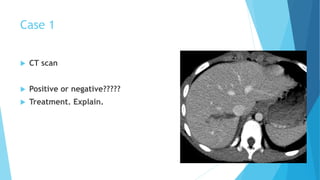

Case 1

 CT scan

 Positive or negative?????

 Treatment. Explain.